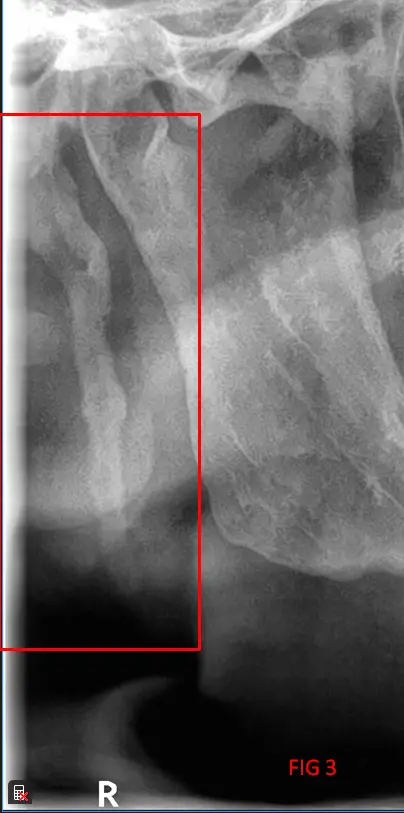

En el análisis de la ortopantomografía, se identifican estructuras radiopacas bilaterales de morfología alargada. Estas formaciones se extienden desde la base del cráneo (apófisis estiloides) con una trayectoria descendente y anterior hacia el hueso hioides (FIG 1, 2 y 3). Basándose en las características imagenológicas, se concluye que se trata de una osificación bilateral del ligamento estilohioideo, un hallazgo que suele presentarse de forma incidental